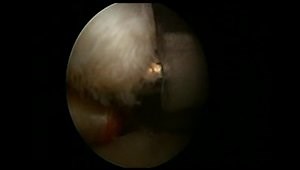

Knotless Arthroscopic Subscapularis Repair

Subscapularis Tears - Classification and Arthroscopic Repair

Arthroscopic Double Row Subscapularis Repair

My Technique: Arthroscopic Subscapularis Repair - Inside View

Arthroscopic Subscapularis Repair: Outside View